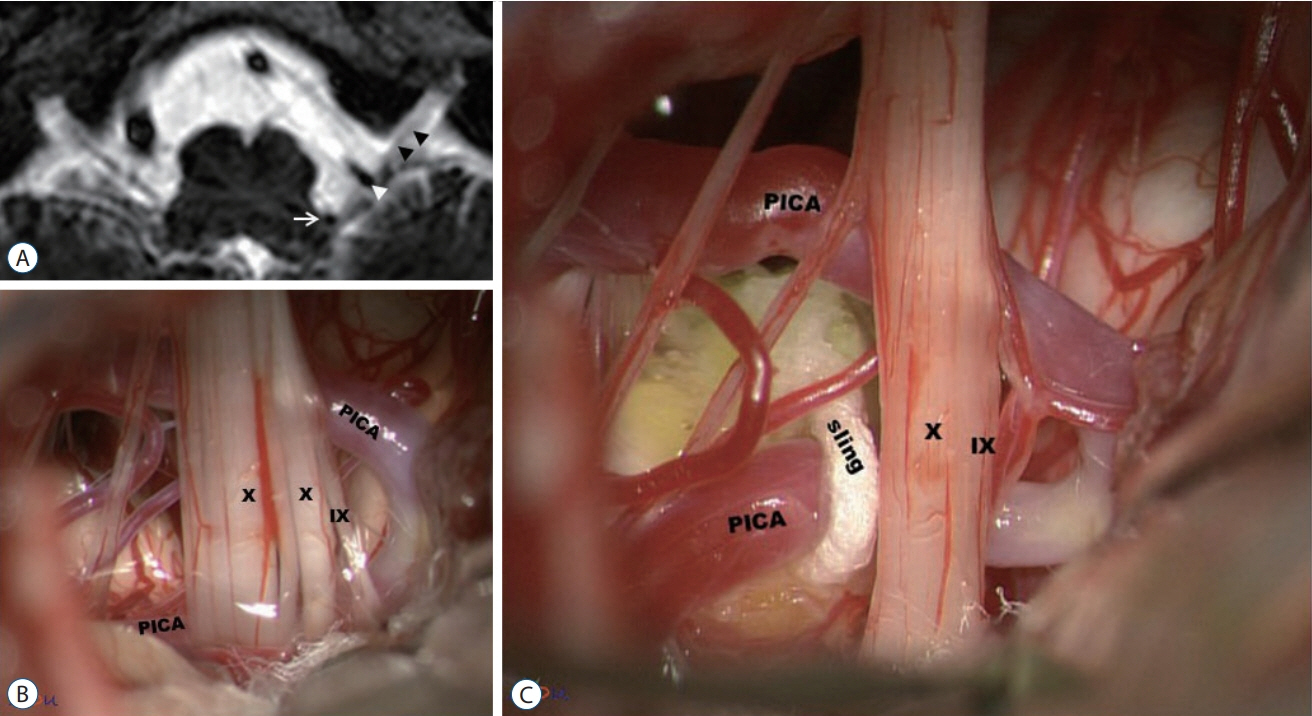

- Glossopharyngeal neuralgia (GPN) is a rare disease that must be differentiated from trigeminal neuralgia. The purpose of this article is to provide a comprehensive review of anatomy, pathophysiology, diagnostic criteria, and several options of treatment for GPN. Lessons learned through our experience of treating GPN are presented in detail, as well as cases of misdiagnosis and diagnostic pitfalls. Microvascular decompression (MVD) should be primarily considered for medically intractable GPN. Techniques employed in MVD for GPN are categorized and described. Especially, we underscore the advantages of the ‘transposition’ technique where insulating material is positioned ‘off’ the root entry zone (REZ), instead of ‘on’ it. We believe this ‘off-the-REZ’ technique can fundamentally prevent recurrence, if applicable. In addition, Gamma Knife radiosurgery can be an alternative option when a patient is ineligible for MVD, though it is categorized as a destructive procedure.